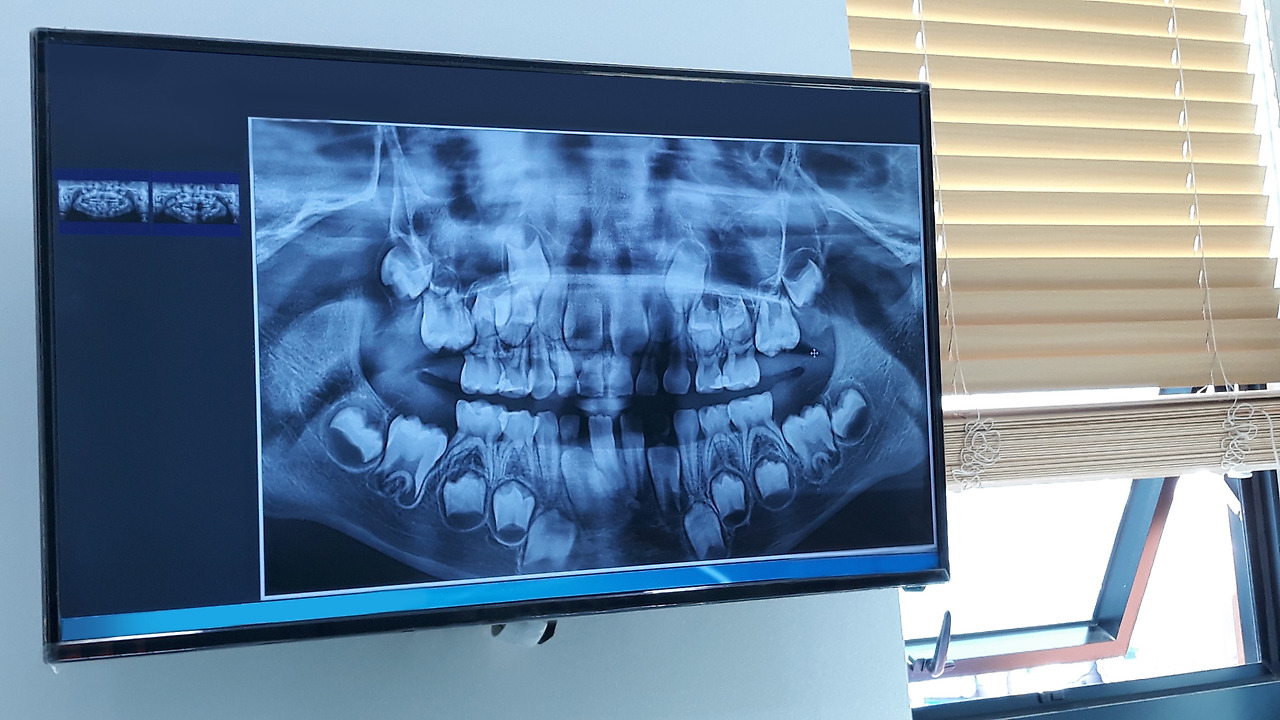

일반적으로 6세경 무렵 영구치가 나기 시작해 7세 정도가 되면 위아래 치아교합이 어느 정도 형성되기 때문에 엑스레이 촬영을 통해 영구치의 배열을 확인하고 교정 시기를 정하는 것이 바람직하죠.